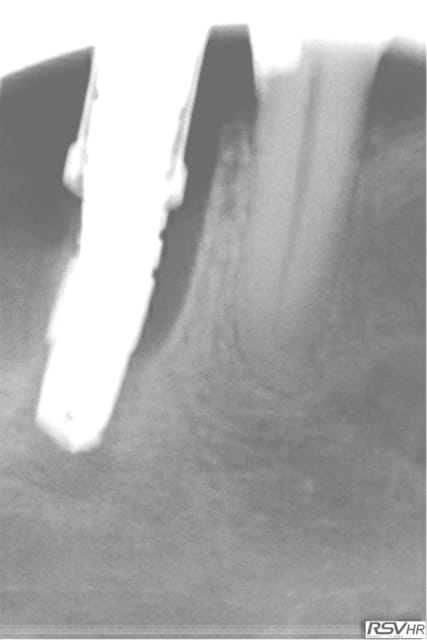

37 fêlure-fracture au niveau du plancher en cours de RTE(1er radio avant RTE)

extraction dans la séance forage entre les racines extraction des racines re- forage après dans le septum

pose implant 7 mm long10mm le 11.06.2012

le 25.09.2012 pose d'un faux moignon titane transvissé et

couronne provisoire

RTE en cours sur 36

CCM définitives après

CBCT en 2014 OK pour l'implant